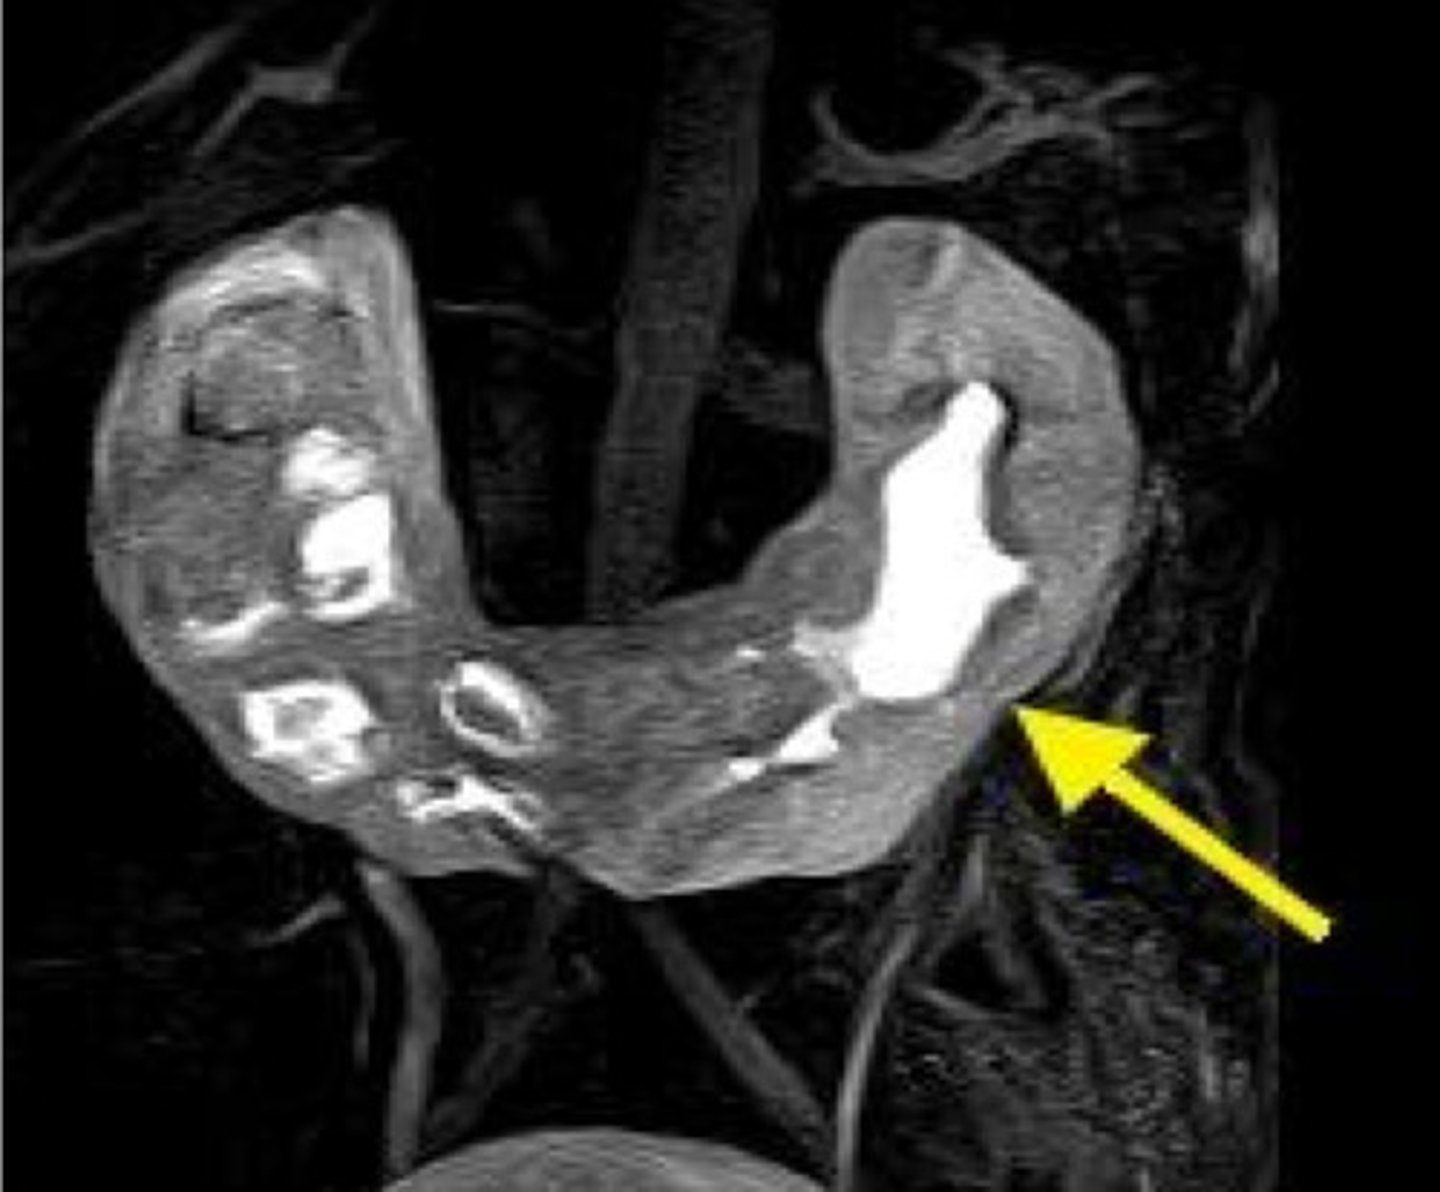

Baby has horseshoe shaped kidneys